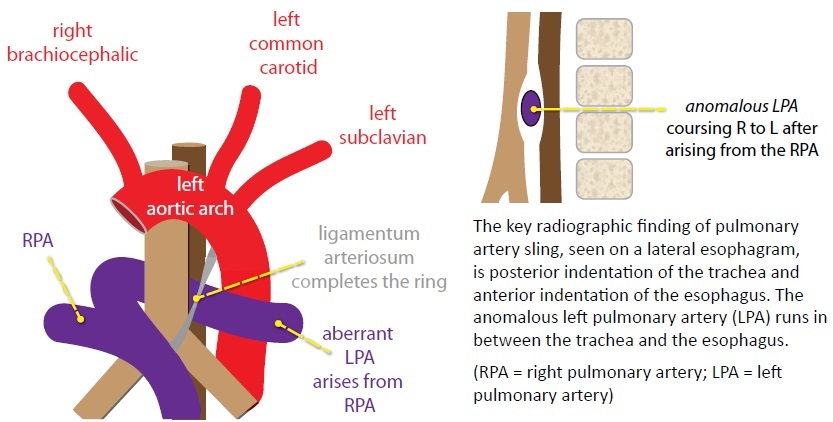

A vascular sling refers to an anomalous course of the left pulmonary artery, which arises aberrantly from the right pulmonary artery adn traps the trachea in a “sling” on three sides.

An important clue to a potential vascular cause of stridor is a right sided aortic arch visualized on the frontal radiograph. The pulmonary artery sling is the only vascular anomaly that causes stridor in a patient with a normal (left) aortic arch.

The three most important vascular causes of stridor are double aortic arch, right arch with aberrant left subclavian artery, and pulmonary sling. Each of these will show abnormality on the lateral radiograph or esophagram.

Pulmonary sling: Anomalous origin of the left pulmonary artery from the right pulmonary artery

An anomalous left pulmonary artery, arising form the right pulmonary artery, forms a sling by coursing in between the trachea and esophagus. Usually only the trachea is trapped in the sling, but occasionally the bronchus intermedius may also be compressed.

Pulmonary artery sling is the only vascular cause of stridor in a patient with a left arch. The aortic branching pattern is normal.

Pulmonary artery sling is associated wtih tracheal anomalies including tracheomalacia and bronchus suis (RUL bronchus originating from trachea).